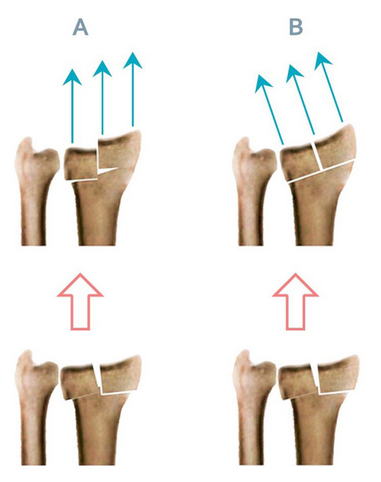

Agee等人先前研究了手掌倾斜恢复极限,他们采用单侧外固定装置进行多平面复位策略。我们试图在术前确定解剖角度,并使用固定角度的EF以避免术中试错,并希望最终确定多平面BEF平面设置的标准。我们假设施加垂直于腕关节的牵引力,而不是平行于桡骨轴的牵引力,可以改善滑脱性,从而减少BEF方法相关的并发症。我们之前的案例系列研究调查了这个问题。根据这一假设,在使用BEF时,牵张力方向的指示调整可以避免平行于关节面施加的剪切力,从而避免桡侧碎片和关节步的移位(图1)。因此,骨折前腕关节倾斜和桡侧倾斜在固定时保持腕关节屈曲和尺侧偏移,可以改善治疗效果。此外,通过调整力的方向,我们可能需要更少的力,减少过度分散的风险。

A - B。外固定定向力的理论修正说明:力平行于半径轴,产生剪切应力,因此关节步骤A,力垂直于桡骨远端关节面,显示更适当的复位B

设计:选取60例不稳定桡骨远端骨折患者,采用分组随机法随机分为两组。A组(第一臂)平行于桡骨轴施加牵引力。在B组(第二臂),根据平均人群健康腕关节的桡侧和掌侧倾斜度调整外固定架,使牵张作用垂直于腕关节面。